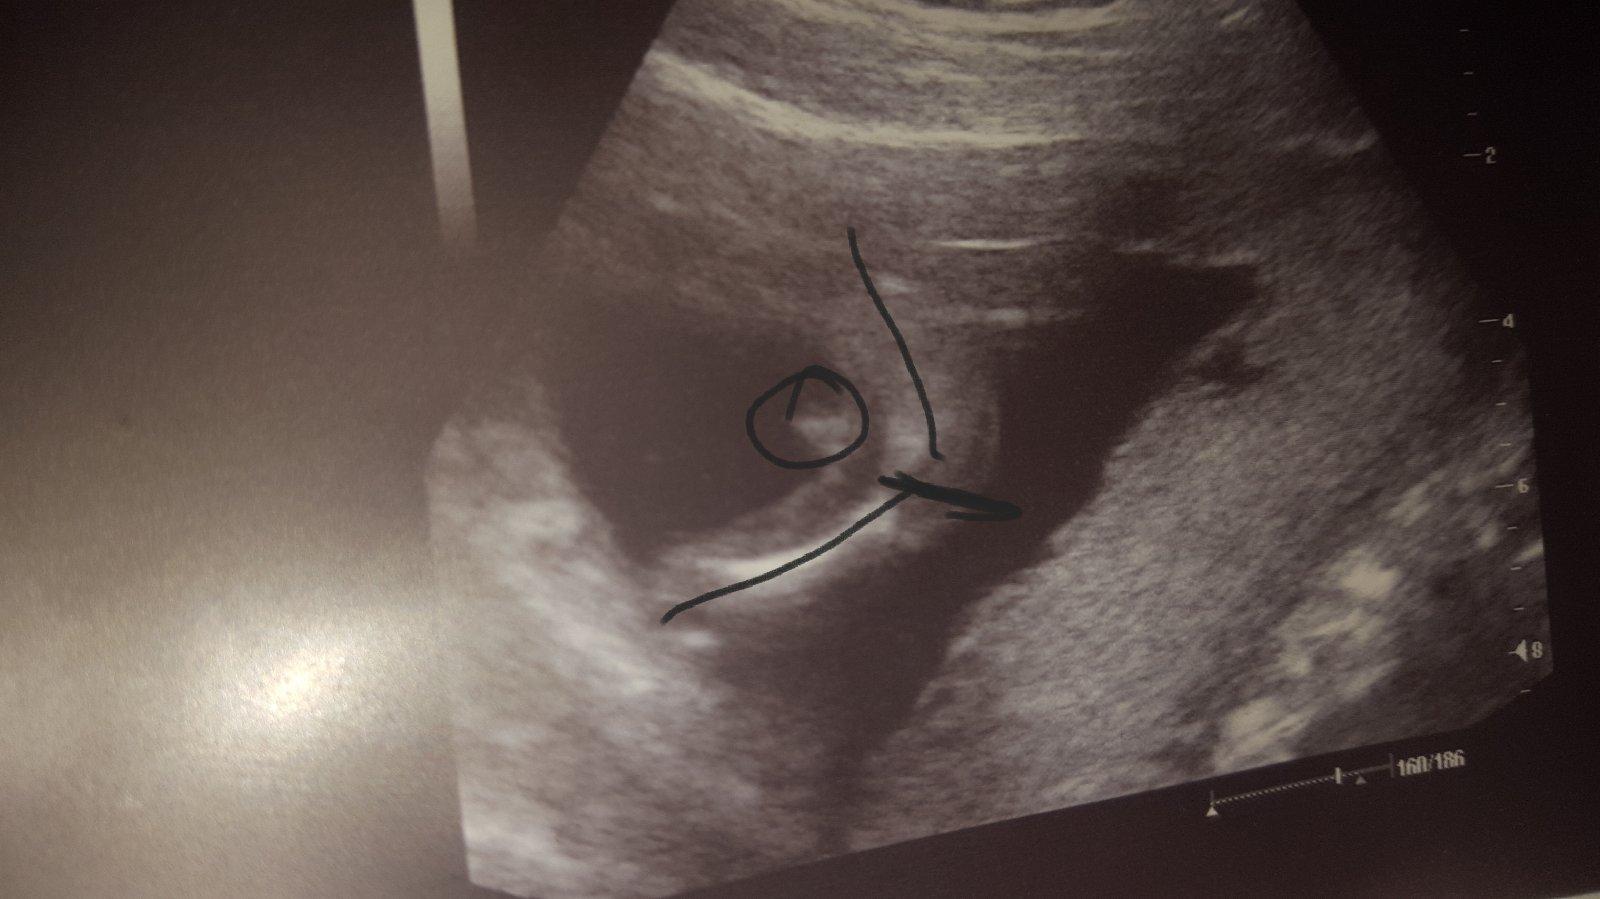

tak já se předevčírem dozvěděla, že čekáme chlapečka a to jsem ve 38. týdnu, za 14 mám jít rodit...doma 70% věcí růžových, protože mi doktorka tvrdila v 5. a 6. měsíci, že je to děvče. Už jsem rodině ani přátelům nic neříkala, ještě se s tím sama srovnávám :D no a vymýšlíme jméno pro chlapce.... i když mám obrázek z ultrazvuku a na něm jasný varlátka a pindík, čekám co z toho nakonec vyjde.... 🙂

@katerinap12 jak to dopadlo? 🙂 ta fotka je celkem srandovní 😀 fakt to působí že má nožky na jinou stranu než pindík

@looolaaa to už je chlap..pindík zretelnej

@lujda661 podle utz to na kluka opravdu vypadá..

@lujda661 jasný kluk, máme stejnou fotku z utz v 16tt a je to kluk 😀